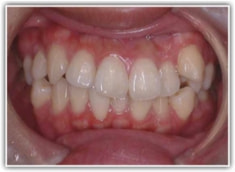

治療後(2年6ヶ月後)

前歯の位置、傾斜、Eラインなど、改善が認められます。

治療後のセファロ分析正貌

非対称が解消されております。